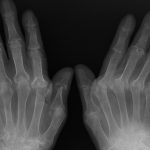

“Le gravi lesioni post-traumatiche riportate dalla paziente a seguito della caduta dalla barella provocarono un significativo peggioramento del suo già compromesso quadro clinico generale. E’ possibile, quindi, ammettere un nesso di causalità materiale tra I’evento traumatico e la morte”. Queste le conclusioni dei medici Maria Francesca Berlich ed Eugenio Vinci, consulenti del pubblico ministero Alessandra Russo (in seguito trasferita alla Procura di Catania) incaricati di fare luce sulle cause del decesso di Carmela Randisi, 81enne di Porto Empedocle caduta da una barella dell’ospedale San Giovanni di Dio di Agrigento (foto).

La donna morì il 30 maggio dell’anno scorso alla clinica Sant’Anna, due giorni dopo essere stata trasferita. Il 14 maggio era arrivata in ambulanza al San Giovanni di Dio per problemi cardiaci. Mentre era in attesa di visita al Pronto soccorso, cadde dalla barella, fratturandosi spalla e femore. Il 28 maggio, dopo un intervento chirurgico, fu deciso il trasferimento alla clinica Sant’Anna per curare meglio i postumi della frattura, ma 48 ore più tardi sopraggiunse il decesso. I consulenti, adesso, scagionano i sanitari della clinica.